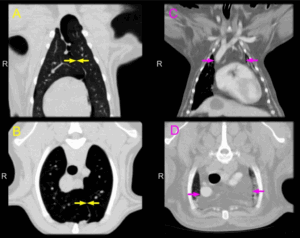

Увеличение тех, которые находятся в труднодоступных местах, можно диагностировать с помощью компьютерной или магнитно-резонансной томографии , ультразвукового исследование. Также всегда назначается общий анализ крови и мочи.

Более подробная диагностика лимфоузлов включает:

- УЗИ; ;

- КТ.